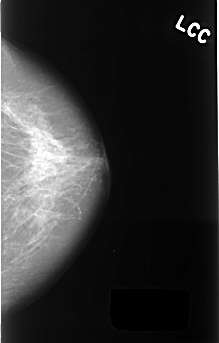

C_0398_1.LEFT_CC

LEFT_CC LINES 4448 PIXELS_PER_LINE 2840 BITS_PER_PIXEL 12 RESOLUTION 50 NON_OVERLAY